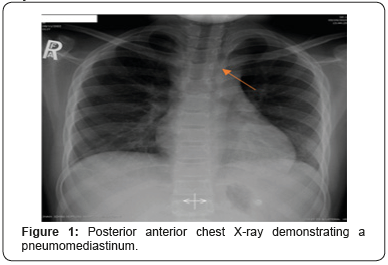

An 11 years old male and his twin brother both were electively admitted for adenoidectomy for obstructive sleep apnea that didn’t respond to medical treatment. The child was otherwise healthy and had no other significant medical history. Under general anesthesia with endotracheal intubation per oral, adenoidectomy was performed using curette and hemostasis was achieved. The surgical steps started after regular smooth intubation, Mouth gag was applied, and nasal catheter was inserted to retract the soft plate. Examination of nasopharynx by mirror revealed moderate adenoid hypertrophy. The adenoid removed by curette and hemostasis was achieved by suction diathermy, the surgical procedure progressed uneventfully. In the recovery room he was doing well apart from mild cough, stable vital signs, he was discharged on the same day. Few hours later at night the patient presented to the emergency room complaining of sever neck pain, stiffness and difficultly in swallowing. A physical examination revealed high temperature, no signs of airway, ventilatory or hemodynamic instability were evident. Laboratory findings included white blood cell (WBC) count of 21,000 cell/ mm3. A lateral neck x-ray showed air leak to retropharyngeal and retromediastinum spaces, with no airway compromise (Figures 1 & 2).